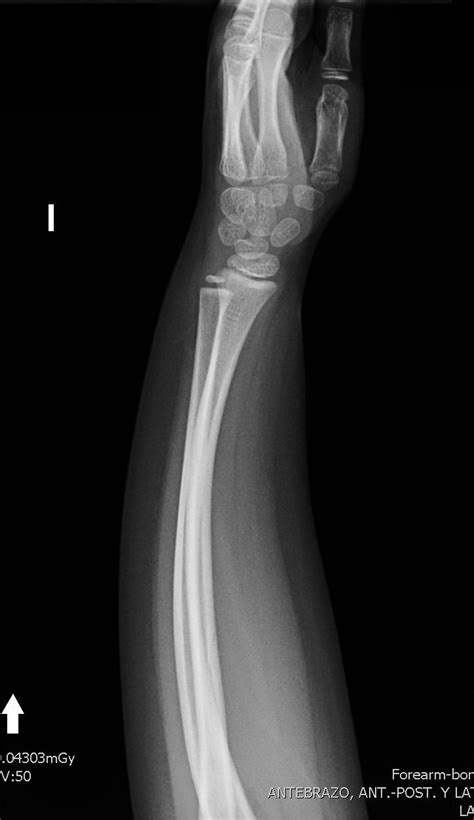

Fractura En Tallo Verde Radio

Fractura En Tallo Verde Radio, , , , , , , 0, Fractura en tallo verde. | Radiografia, Fractura, Verde, www.pinterest.com.mx, 1080 x 1920, jpeg, WebUna fractura en tallo verde es una fractura de espesor parcial, que implica una fractura completa de la corteza y el periostio en solo 1 lado del hueso. La. WebLas fracturas en tallo verde, son fracturas incompletas que se dan en un hueso largo de un niño que no ha terminado de crecer. En estos casos, la fractura se., 20, fractura-en-tallo-verde-radio, Novedades y Muebles WebUna fractura en tallo verde es una fractura de espesor parcial, que implica una fractura completa de la corteza y el periostio en solo 1 lado del hueso. La. WebLas fracturas en tallo verde, son fracturas incompletas que se dan en un hueso largo de un niño que no ha terminado de crecer. En estos casos, la fractura se.

WebLa fractura en tallo verde es una lesión que se suele producir en muchos niños que aún están en pleno crecimiento. Se trata de una fractura o rotura. WebSegún la localización de la fractura tenemos que pueden afectar a la metáfisis, a la diáfisis, al cartílago de crecimiento o a la epífisis (Anexo 1). Las fracturas. WebSe denomina «en tallo verde», ya que la fractura se asemeja a la rotura de una rama viva y «verde», en la que un lado del palo permanece intacto. Presenta un. WebFRACTURAS EN TALLO VERDE: El grosor perióstico y la elasticidad del hueso de los niños hace que en ocasiones la fractura se produzca sólo en el lado de la convexidad. WebFRACTURA EN TALLO VERDE Tratamiento: Consistirá en la reducción del desplazamiento entre los fragmentos. Para ello deberá convertirse la fractura en completa, fracturando la. WebLa fractura en tallo verde de la ulna no se trata y se realiza un ostectomía de... Estabilización de fractura Salter I del radio con dos alambres K en paralelo.

WebFRACTURA EN TALLO VERDE Tratamiento: Consistirá en la reducción del desplazamiento entre los fragmentos. Para ello deberá convertirse la fractura en completa, fracturando la. WebLa fractura en tallo verde de la ulna no se trata y se realiza un ostectomía de... Estabilización de fractura Salter I del radio con dos alambres K en paralelo. WebFracturas en rodete o caña de bambú: Estas fracturas se producen con las caídas sobre la palma de la mano. En este caso el hueso se “aplasta” y se ensancha,.